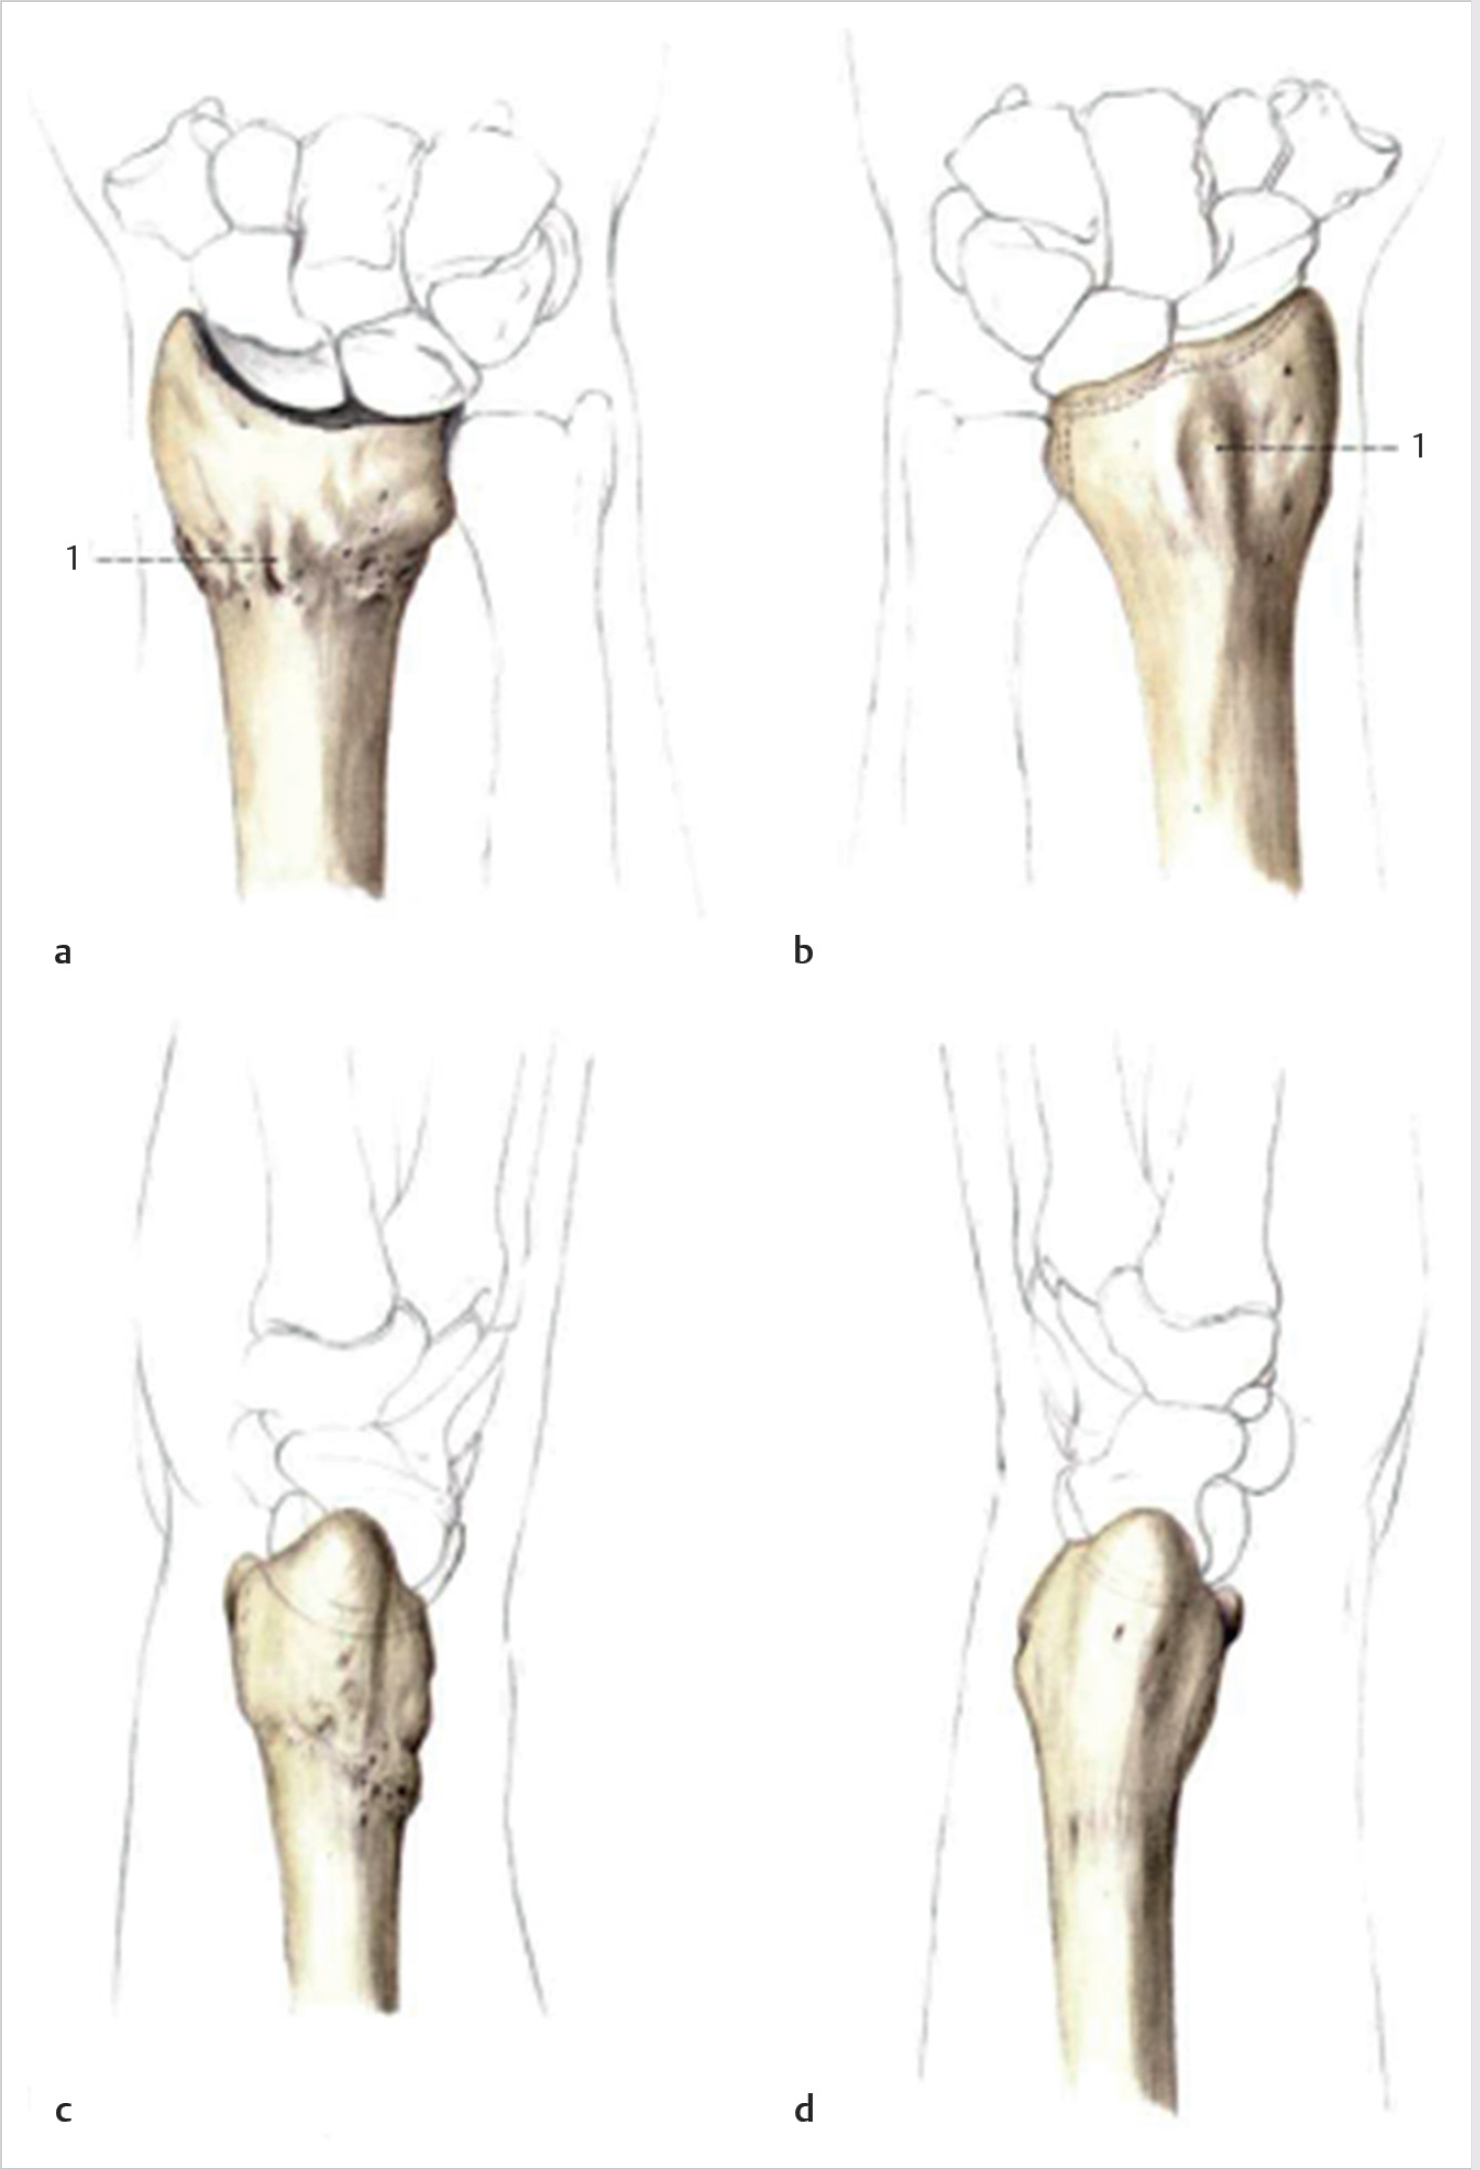

Fractures of the distal radius are one of the most common skeletal injuries of the upper extremity. Fracture malunion is a common complication, occurring in approximately 5% of cases of all the distal radius fractures (► Fig. 53.1). 1 In some cases, malunions can be asymptomatic and do not require treatment. In some cases, however, the bony position can lead to pain, loss of motion, and reduction of the grip strength, leading to poor functional outcomes. 2 , 3 , 4 Loss of radial length and disruption of the articular surface are radiographic parameters leading to symptomatic malunion. 5 In symptomatic cases refractory to conservative treatment, corrective osteotomy of the fracture can often provide pain relief, improved kinematics, and functional outcomes. 6 Various techniques including opening or closing wedge osteotomies with or without bone grafting have been described. 7

Especially when multiplanar and intra-articular deformities are present, corrective osteotomies are technically challenging procedures. Preoperative planning with comparison of the bony anatomy with the normal, contralateral side can be helpful (► Fig. 53.2). Computerized tomographic (CT) scanning can add useful information in the preoperative stage, especially in fractures with an articular component. 10

Preoperative planning is essential for intraoperative decision making. Desired angles for correction are determined corresponding to the opposite side (► Fig. 53.4). Using templated X-rays to assess length, osteotomy location, and osteotomy or either printing out X-rays and constructing osteotomies on the paper to determine appropriate cut locations, angles, and center of rotation can be very helpful (► Fig. 53.5). CT-derived threedimensional bone models can allow for preoperative planning.

Two methods for preoperative planning have been described by Nagy and Fernandez on the basis of plain X-ray (► Fig. 53.6). Intra-articular and rotational deformities are difficult to assess on radiographs; the use of three-dimensional imaging and patient-specific guides can help the challenge. 16 , 17